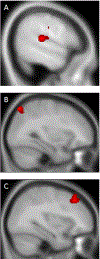

The gut microbiota has recently gained attention as a possible modulator of brain activity. A number of reports suggest that the microbiota may be associated with neuropsychiatric conditions such as major depressive disorder, autism and anxiety. The gut microbiota is thought to influence the brain via vagus nerve signalling, among other possible mechanisms. The insula processes and integrates these vagal signals. To determine if microbiota diversity and structure modulate brain activity, we collected faecal samples and examined insular function using resting state functional connectivity (RSFC). Thirty healthy participants (non-smokers, tobacco smokers and electronic cigarette users, n = 10 each) were studied. We found that the RSFC between the insula and several regions (frontal pole left, lateral occipital cortex right, lingual gyrus right and cerebellum 4, 5 and vermis 9) were associated with bacterial microbiota diversity and structure. In addition, two specific bacteria genera, Prevotella and Bacteroides, were specifically different in tobacco smokers and also associated with insular connectivity. In conclusion, we show that insular connectivity is associated with microbiome diversity, structure and at least two specific bateria genera. Furthemore, this association is potentially modulated by tobacco smoking, although the sample sizes for the different smoking groups were small and this result needs validation in a larger cohort. While replication is necessary, the microbiota is a readily accessible therapeutic target for modulating insular connectivity, which has previously been shown to be abnormal in anxiety and tobacco use disorders.